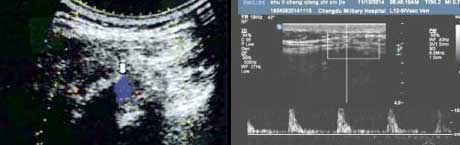

三、准确检测骨质细微病变,辅助评估骨质受损程度

肌骨超声不仅能够较好地显示关节及周围软组织的病理改变,还能清晰地显示骨皮质表面附着端的异常和骨性水肿,检测到骨和软骨表面的细微病变、小的骨质缺损。此外,在超声影像下,肌腱所附着的关节处骨皮质破坏、骨质糜烂,“虫蚀样”改变,邻近骨质的反应性硬化及绒毛样改变,关节软骨与滑膜交界处骨轮廓“火山口”样缺损,软骨透明度的丢失和软组织界面完整性的丢失情况都均能清晰显示。通过研究证实,超声对肌腱及其附着处骨皮质的观察,有利于更准确的评估AS患者外周关节的骨质破坏程度,进而判断病情严重程度。

软骨损伤

AS患者骨皮质中断、不连续,可见到游离骨片

骨质钙化受、改变

肌腱附着处滑囊内伴积液,呈“虫蚀样”改变、见钙化灶